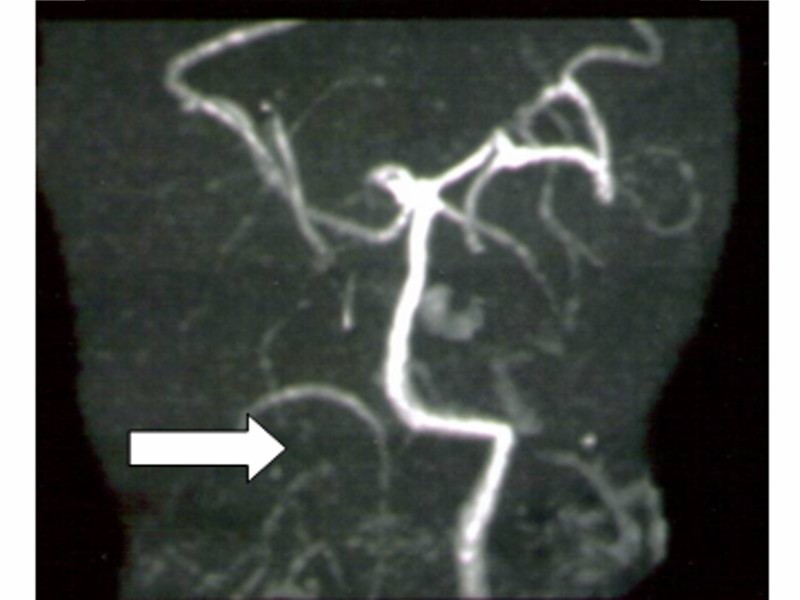

この結果再度画像診断が行なわれ、①C3・C4レベルの頸椎の変形(図3)、および②右側椎骨動脈の低形成とが指摘された。図4は、脳外科の回答後にわれわれが立ち合って撮影しなおしたMRAで、図5に模式図として示したように右側椎骨動脈の低形成が認められる。

図4